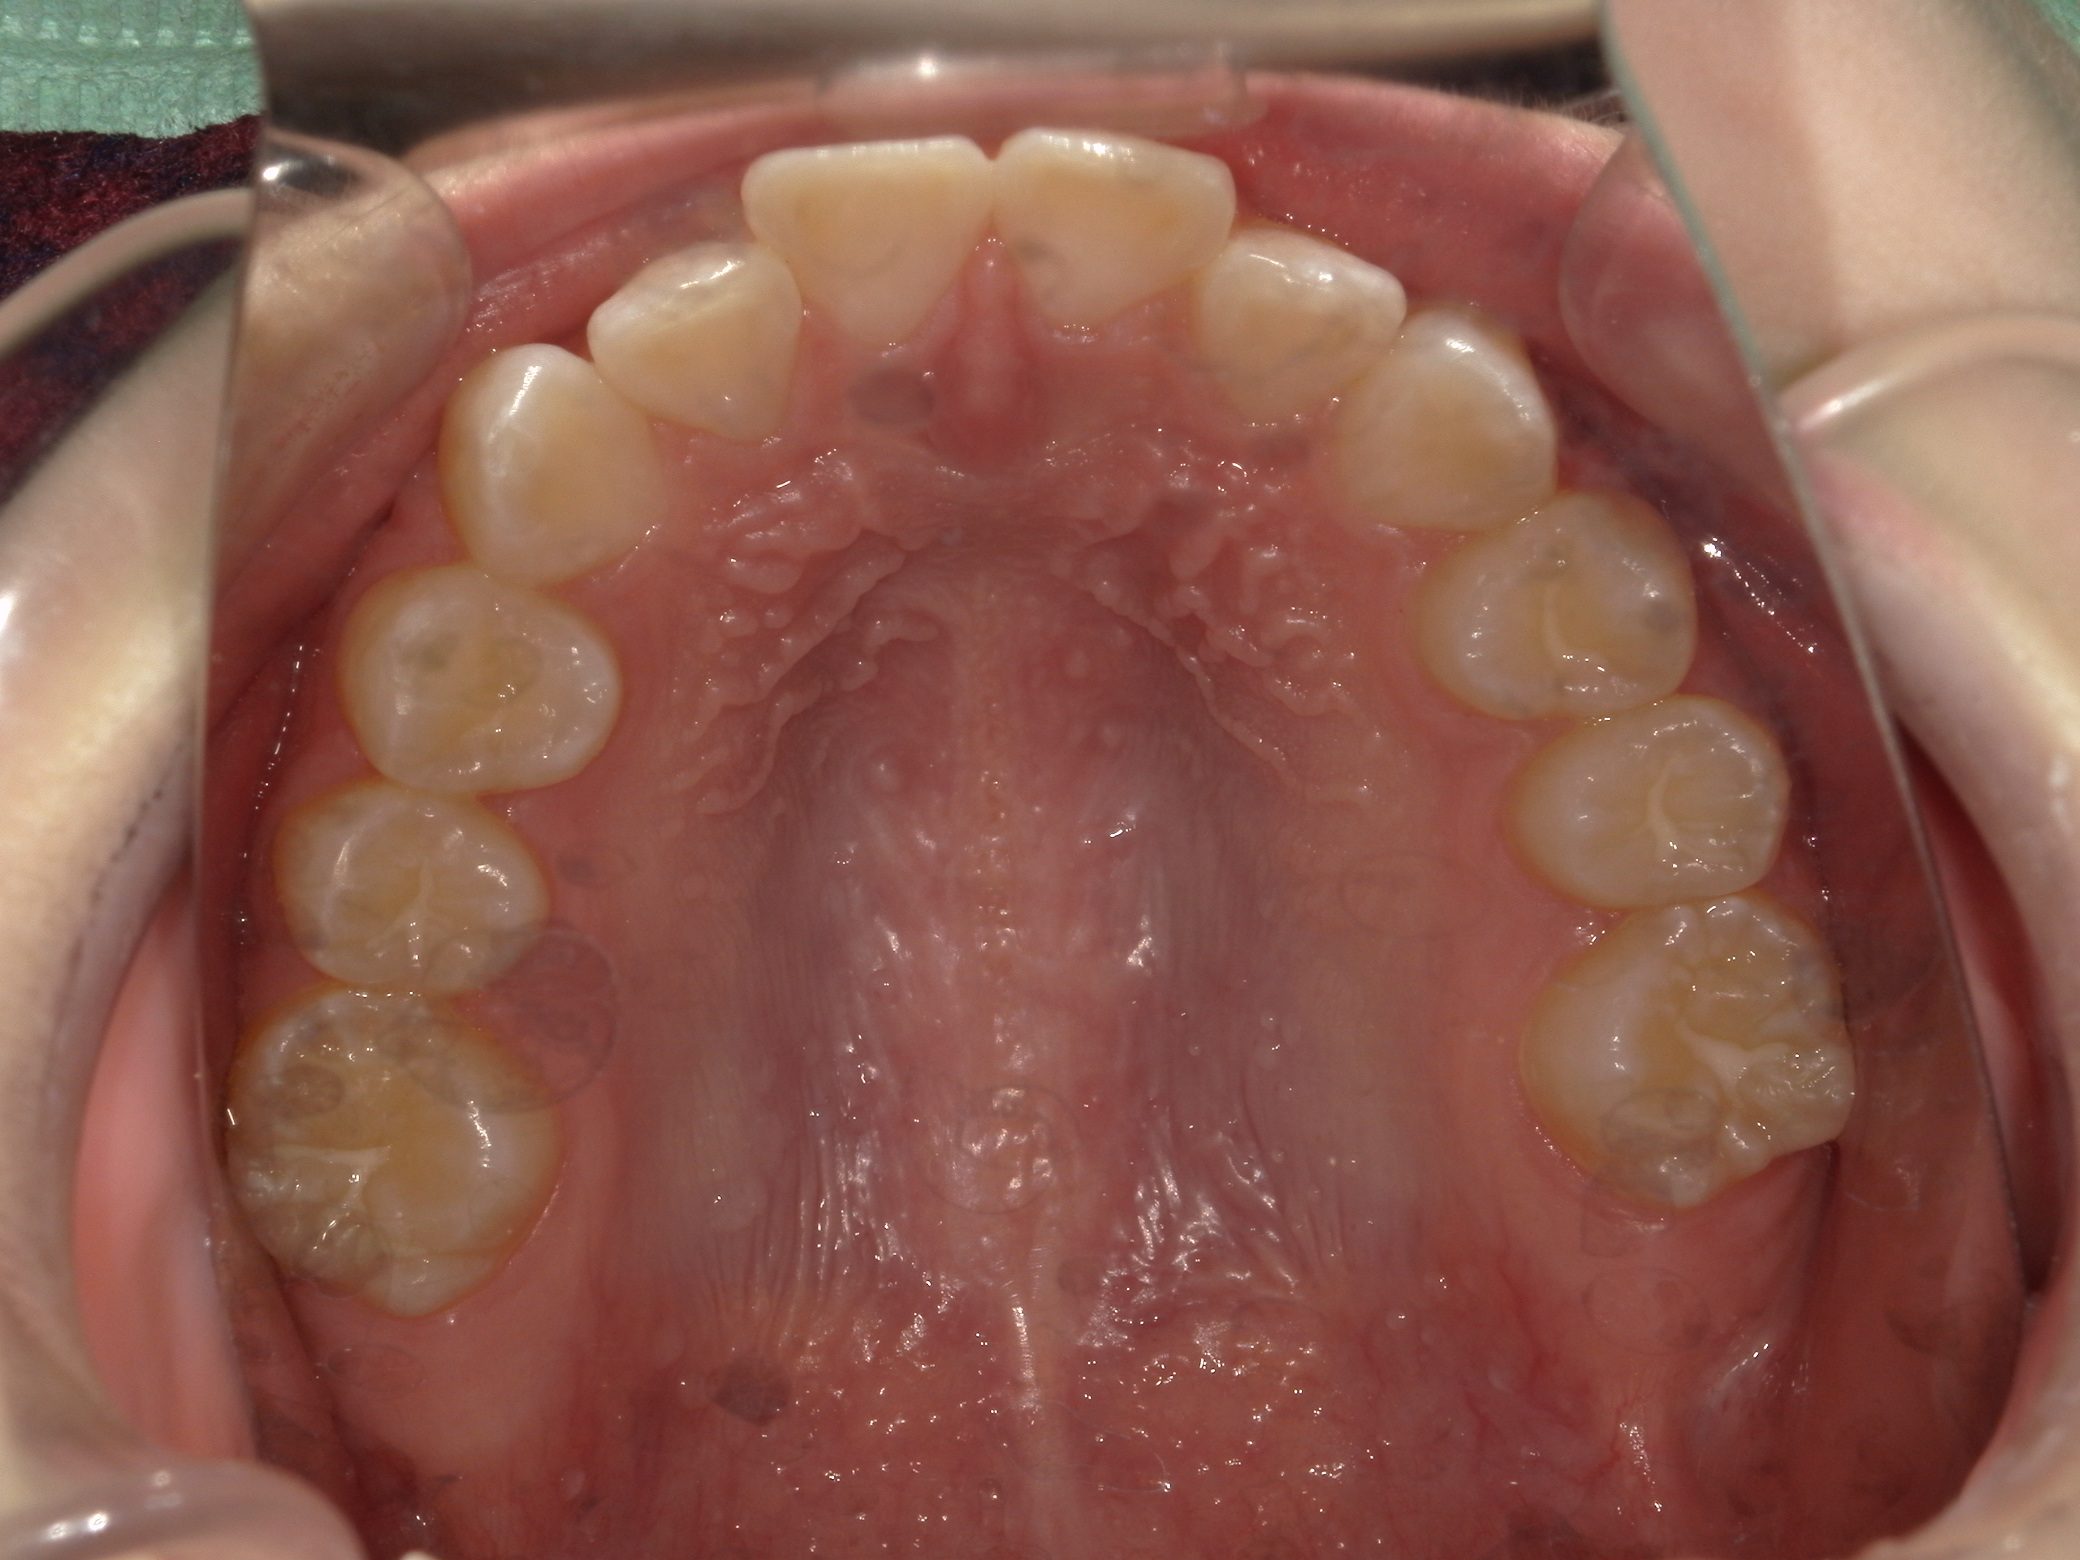

【中学生】インビザラインフル 先天欠損歯あり 叢生(でこぼこ) を改善

中学生以降

インビザライン フル

でこぼこ

過蓋咬合

非抜歯

2期治療のみ

Before

After

治療期間

10か月年

治療開始

14歳

種類

インビザライン矯正

使用装置

インビザラインフル

コメント

下顎の前歯が生まれつき1本少ないので

過蓋咬合になりやすい歯並びです

咬み合わせの深さを改善することと

下顎の叢生(でこぼこ)を改善すること

奥歯の咬み合わせを 歯が1本少なくても しっかり作り上げること

この3つを実現して治しています。